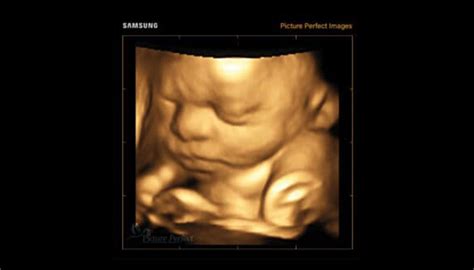

Umana Fertility oferă servicii medicale complete de reproducere umană asistată, începând cu primele investigații necesare diagnosticului și până la procedurile de inseminare intrauterină și fertilizare in vitro. Facem din fiecare poveste povestea noastră și ne bucurăm alături de fiecare cuplu care își îndeplinește visul de a avea un copil cu ajutorul procedurilor de fertilizare in vitro.

Oferim servicii medicale complete de reproducere umană asistată, începând cu primele investigații necesare diagnosticului (ecografii, histeroscopii, HyCoSy, spermograme, evaluări nutriționale, suport psihologic și multe altele) și până la procedurile de inseminare intrauterină și fertilizare in vitro, alături de tehnici speciale de laborator, special concepute să ofere pacienților cele mai bune șanse de reușită.